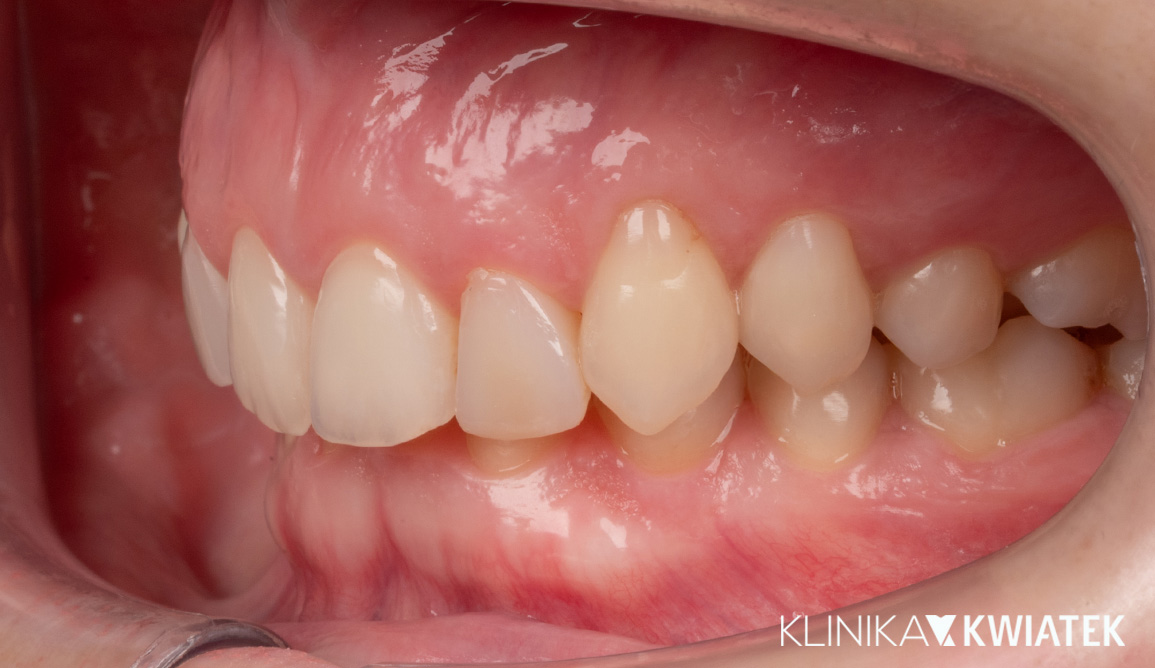

Kompleksowe leczenie i odbudowa funkcji – droga do pięknego uśmiechu

Do naszej Kliniki zgłosił się Pacjent z poważnymi problemami stomatologicznymi – licznymi ubytkami, nieprawidłowym zgryzem oraz widocznym starciem zębów, co wpływało na estetykę i funkcję. Przeprowadziliśmy kompleksowy plan leczenia: od diagnostyki, higienizacji i leczenia zachowawczego, przez szynoterapię i leczenie implantologiczne, aż po pełną odbudowę protetyczną. Efekt końcowy to zdrowy, harmonijny uśmiech oraz pełny komfort w codziennym funkcjonowaniu.